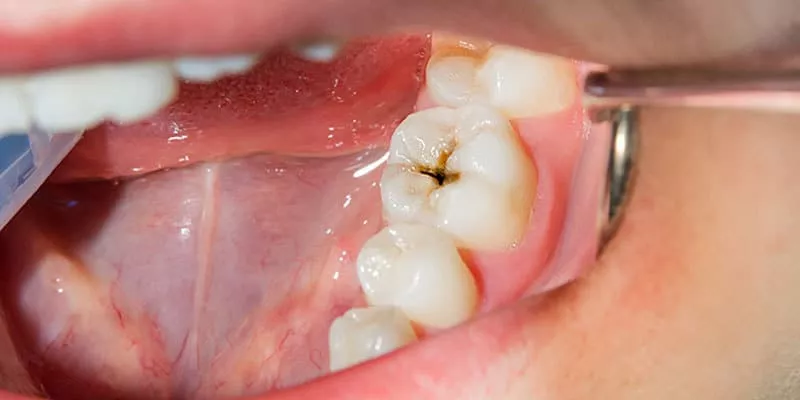

Dental caries is a condition that occurs when bacteria is deposited and when food debris (especially simple sugars) is broken down and converted into acids that create cavities. When these cavities are deep, they affect the dental pulp (the nerve of the tooth) causing pain, infection, and in some cases, fractures that can lead to the loss of the tooth.

It is a common belief that if part of the tooth structure has been replaced by an inert material, it will not suffer any damage. The truth is, although crowns are not affected by caries, the dental remnant underneath can still deteriorate.

- Dthat adaptation between prosthesis and tooth: A “critical zone” is created by the union of the crown and the tooth, mediated by a special cement. Over the years, this cement can disintegrate and generate small spaces that lead to the leakage of bacteria and food debris under the crown, generating”recurrent caries” or “secondary caries”.

Cavities under crowns are usually hard to identify, even during a dental consultation since most are not perceptible to the naked eye. In many cases, cavities under crowns are detected thanks to X-rays. It is extremely important to know the symptoms of this condition and seek dental care in case of presenting them.